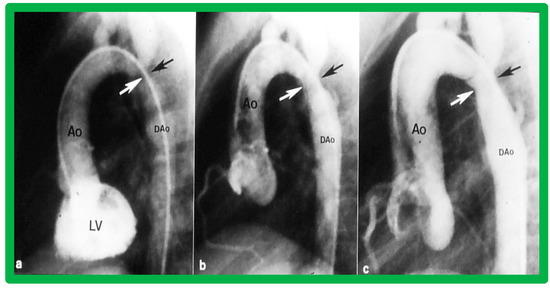

3.2. Aortic Stenosis

4.2. Aortic Stenosis

5.2.1. Causes of Restenosis

5.2.2. Feasibility of Repeat BAV to Address Recurrence of AS